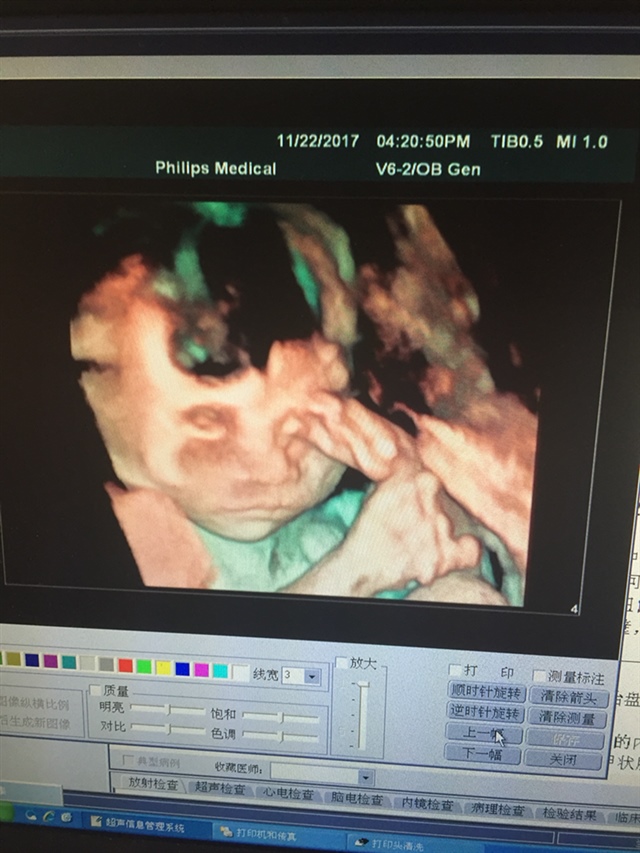

宝宝4个月3天

像你老公多点,在揉眼睛好可爱啊